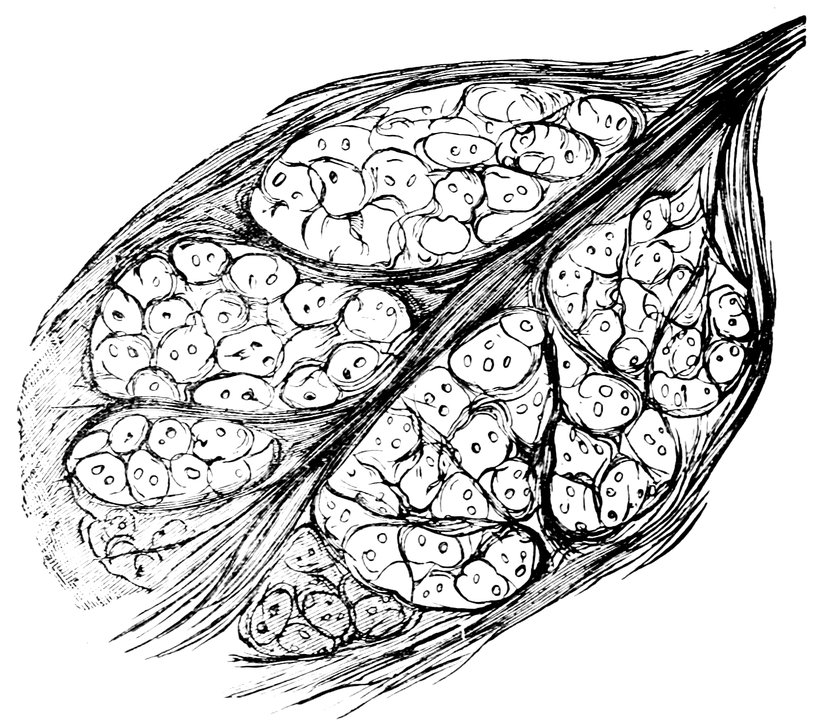

| 15. | Primitive follicles | 58 |

| 16. | Ripening follicles | 61 |

| 17. | Graafian follicles | 62 |